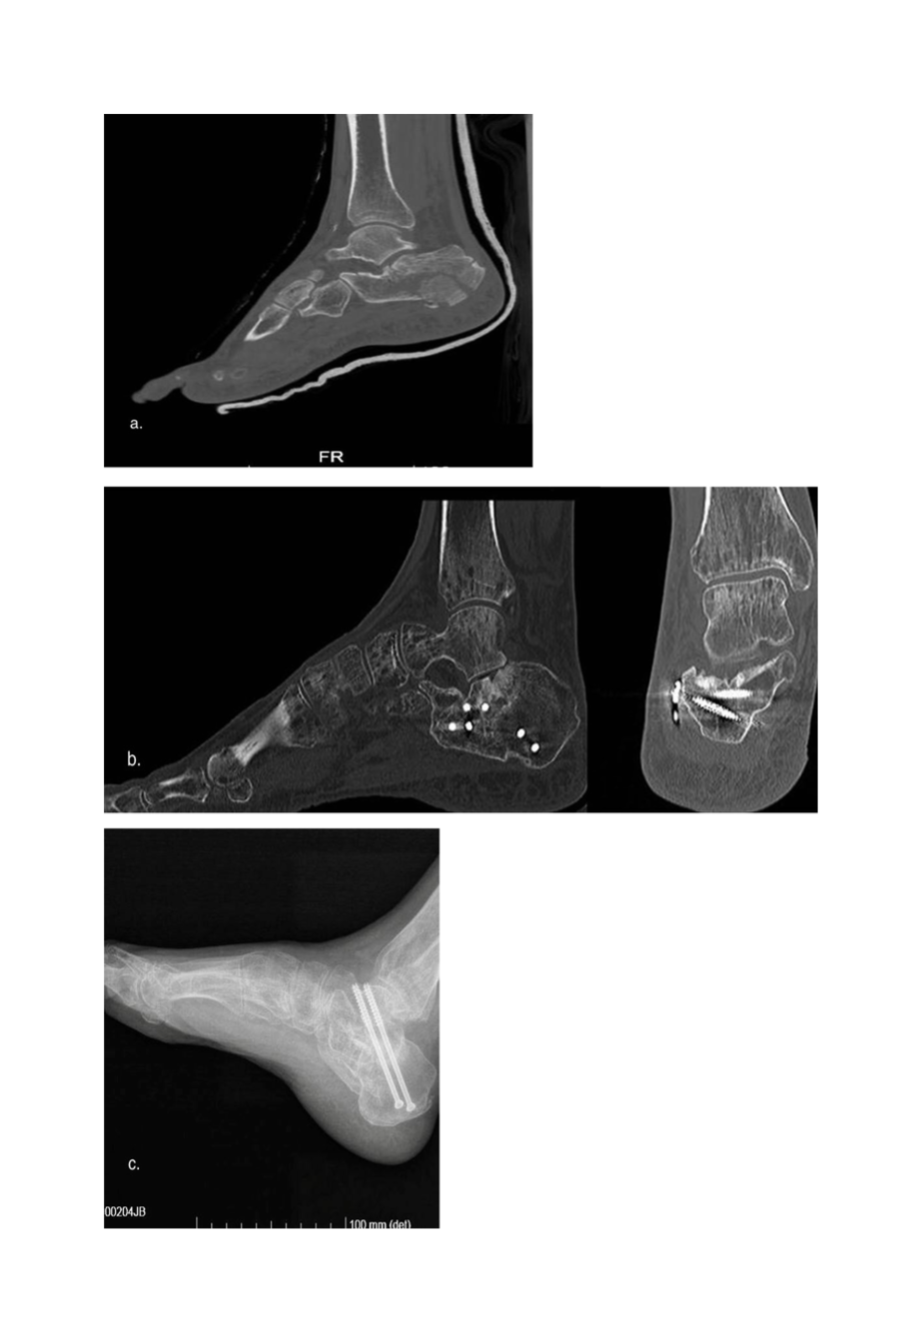

Postoperative complications included one case of algodystrophy in the LP group, resolved with clodronic acid and pulsed magnetic field therapy. Three cases of chronic peroneal tendinitis were resolved by removing the plate and screws after bone healing, and one patient underwent secondary subtalar arthrodesis due to osteoarthritis 3 years after the injury (Figure 6a-c). Only four patients resumed sports activity (two from each treatment group).

Figure 6. a, preoperative CT scan, man 56 y, (b) CT scan after 30 months, (c) post-operative (secondary subtalar arthrodesis) X-ray.